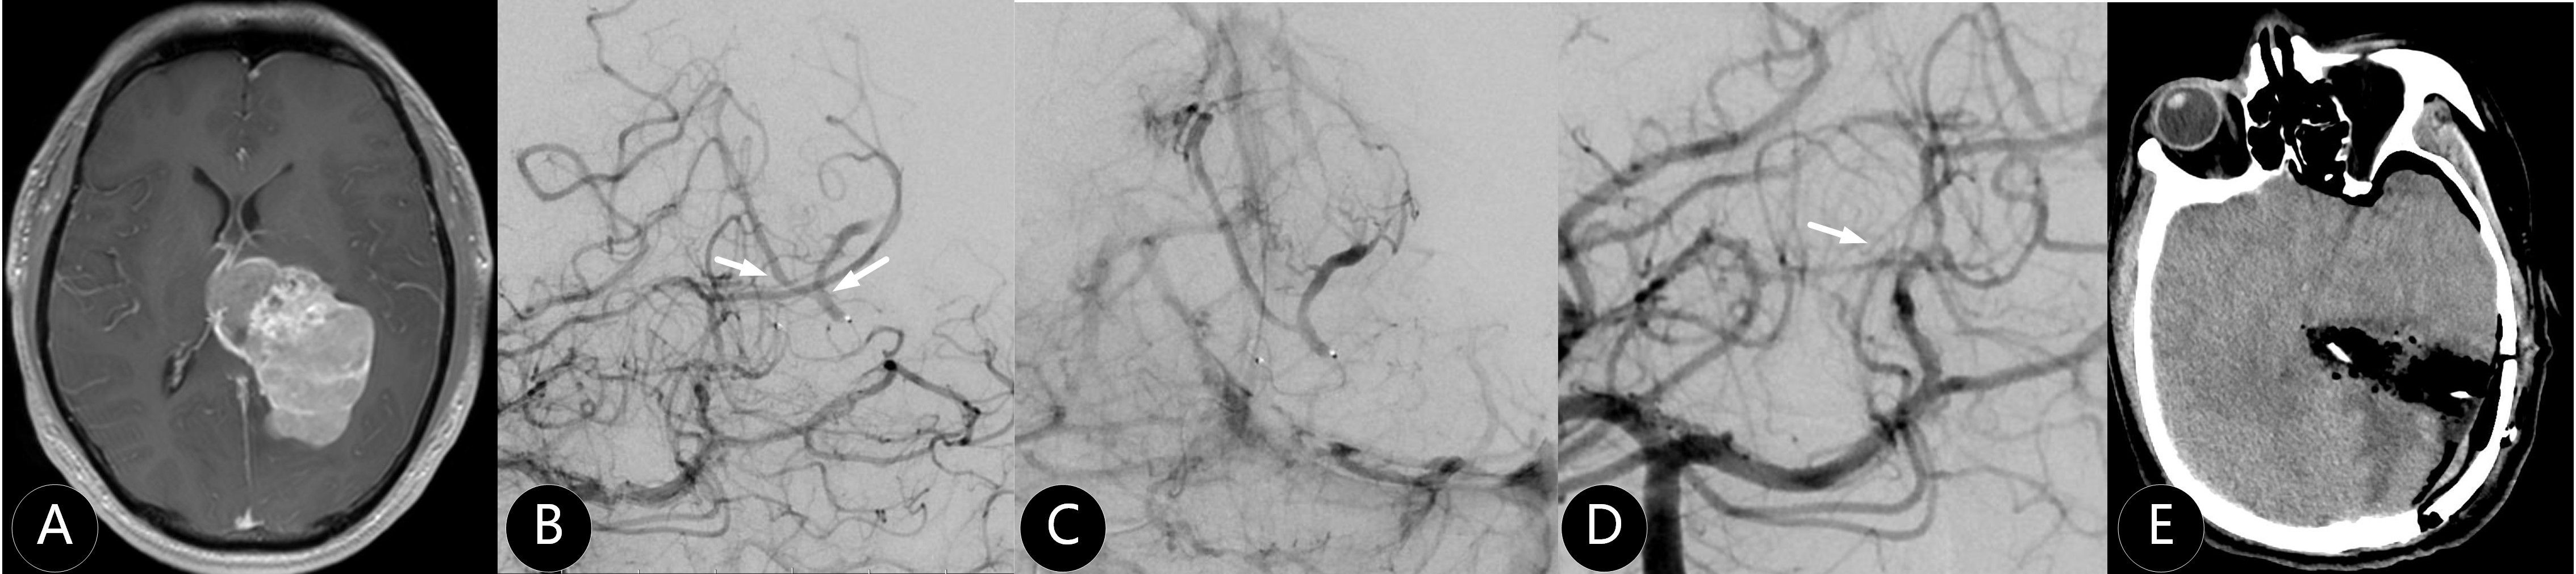

Background Preoperative embolization has been proposed to reduce intraoperative blood loss and facilitate meningioma resection, however its clinical utility remains debated. This multicenter study evaluated the safety, efficacy, and angiographic outcomes of preoperative embolization and standalone embolization in intracranial meningiomas. Methods In this retrospective cohort from January 2017 to January 2022, patients were stratified into three groups: standalone embolization (SE), combined preoperative embolization and craniotomy (hybrid surgery, HS), and craniotomy alone (control). Tumor characteristics, procedural metrics, and clinical outcomes were compared. Results: Compared to control group, the HS group exhibited significantly larger tumors (68.8±10.6 cm³ vs 35.7±11.3 cm³, P<0.001) but achieved reduced intraoperative blood loss (9.8±2.3 mL/cm³ vs 19.2±6.5 mL/cm³, P<0.001) and higher gross total resection rates (70.1% vs 46.2%; P=0.025). Compared to HS group, the SE cohort had smaller tumor volume (24.7 ± 5.2 cm³ vs 68.8 ± 10.6 cm³; P<0.001), better baseline neurological function score (median mRS 0 vs 1; P<0.001), and showed higher total devascularization rate (56.3% vs 25.4%; P=0.008) after embolization procedure. Tumors in SE group were supplied exclusively by the external carotid artery (ECA). At a median 24-month follow-up, recurrence rates and neurological change were no different across groups. Conclusion Hybrid surgery optimized surgical resection for large meningiomas by reducing blood loss and improving resection completeness, while standalone embolization demonstrated feasibility for select small tumors with ECA. Both two strategies showed acceptable safety and effectiveness.